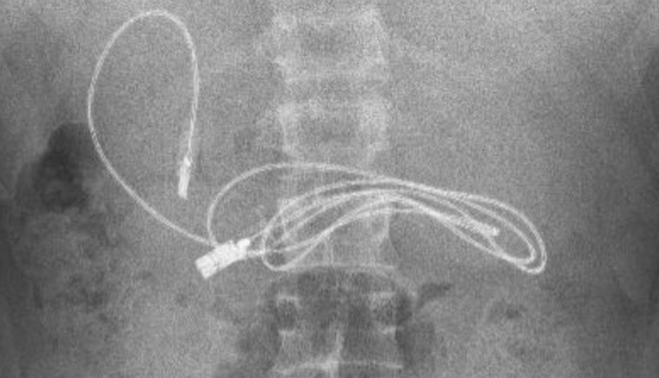

Se quedaron con la boca abierta cuando en la radiografía se podía divisar claramente estos dos objetos. De inmediato, el joven fue trasladado a un especialista, concretamente al hospital de Firat en Elazig, donde el jefe del departamento de gastroenterología, hepatología y nutrición pediátrica no podía creer que el menor tuviera en su interior semejantes objetos.

Ante esta situación, fue intervenido con el fin de extraer el cable y la goma lo antes posible. Los médicos han compartido en sus redes sociales la sorprendente radiografía y explicaron que el médico realizó una endoscopia a través de su boca para llegar al punto donde se encontraba el cable. Según recoge Telecinco, fue una tarea complicada porque uno de los extremos había pasado al intestino delgado.